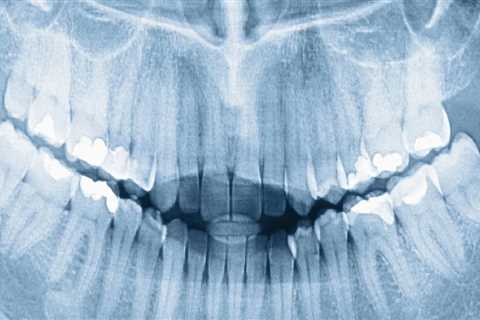

The Role of Dental X-Rays in Orthodontics in Seattle

Discover how dental X-rays ensure safe orthodontic care at Koh Orthodontics in Seattle, WA.